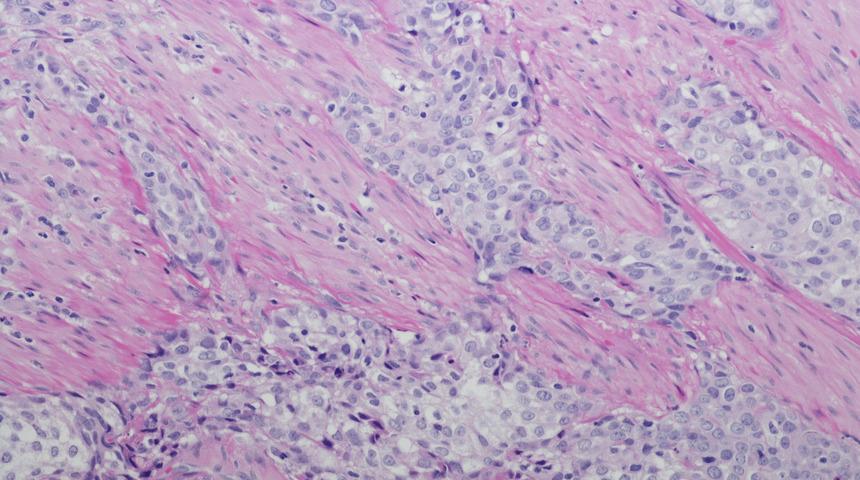

Üroloji Uzmanı Prof. Dr. Yener Gültekin tanının son derece önemli olduğunu kaydedip, “Hastalığın görülme sıklığı yaşla birlikte artar, ülkemizde 50-69 yaş erkeklerde en sık görülen kanserler içinde dördüncü sırada yer alırken 70 yaş ve üzerinde üçüncü sıraya yükselmektedir. Mesane kanseri tanısında hastanın şikayetlerinin ayrıntılı sorgulanması, sigara kullanımının ve kimyasallara maruziyetinin bilinmesi önemlidir. Hastalığın görüntülenmesinde ultrasonografi, bilgisayarlı tomografi, ve sistoskopi önemlidir. Sistoskopi, mesanenin bir alet yardımıyla doğrudan gözle görülmesini sağlayan yöntemdir. Hem tanı hem de tedavi amacıyla kullanılır tanı için parça almasını ve çoğu kez de kanserli dokunun tedavisi için kazınarak çıkarılmasını sağlar” dedi.

“Mesane kanserlerini yüzde 75’i ilk tanı konulduğunda yüzeyseldir, yani kanser mesane adalesine yayılmamıştır. Bu evrede etkin tedavi ve yakın takiple kişi mesanesi ile yaşama şansına sahip olabilir. Mesane adalesi tutulmuş ancak başka organlara yayılmamışsa mesanenin cerrahi olarak çıkarılmasıyla gerekir. Yayılma varsa kemoterapi ile tedavi edilmeye çalışılır.”